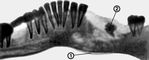

В сенсибилизированном организме при распространении патологического процесса в губчатое вещество кости развивается острый одонтогенный остеомиелит — гнойно-некротическое воспаление, чаще возникающее в нижней Ч. Заболевание развивается бурно, сопровождается высокой температурой тела, ознобом, значительными изменениями со стороны крови. В процесс быстро вовлекаются здоровые зубы: они становятся чувствительными к прикосновению, подвижными. На поверхности кости появляется разлитой инфильтрат, в окружающих мягких тканях часто развиваются абсцессы, флегмоны. При локализации процесса в боковых отделах тела нижней челюсти (зона иннервации подбородочного нерва) часто нарушается или утрачивается чувствительность половины нижней губы и подбородка вследствие сдавления нерва воспалительным инфильтратом или неврита. Острая стадия при значительной распространенности процесса, как правило, длится 10—14 дней и, если не наступает выздоровления, переходит в хроническую. Пораженные участки кости некротизируются и подвергаются секвестрации: вокруг погибшего участка кости формируется так называемая секвестральная капсула. Образуются свищи, через которые выделяется гной. Свищи могут открываться в полости рта, на лице, шее. Свободное выделение гноя сопровождается улучшением общего состояния, нарушение оттока приводит к обострению болезни, усилению интоксикации. С ликвидацией воспалительного очага свищи самостоятельно закрываются, иногда образуя втянутые рубцы. Диагноз устанавливают на основании клинической картины, лабораторного и рентгенологического исследований. Рентгенологические признаки остеомиелита выявляются через 8—14 дней от начала заболевания. Вначале отмечается нечеткость рисунка костной ткани, позже — очаги деструкции (секвестральные полости) с секвестром в центре (рис. 1). Лечение при остром остеомиелите Ч. включает раннее удаление зуба, послужившего источником воспаления, широкое вскрытие инфильтратов и гнойных очагов в надкостнице и окружающих мягких тканях, трепанацию кортикальной пластинки челюсти в области очага некроза (компактотомию), комплекс противовоспалительных мероприятий, обычно применяемых при остеомиелите. Однако это не всегда приводит к купированию процесса, а лишь облегчает его течение. При хроническом остеомиелите лечение оперативное. Для предупреждения патологических переломов уже на ранних стадиях заболевания на Ч. накладывают назубные или наддесневые шины. Подвижные зубы удалять не следует; их скрепляют шиной.